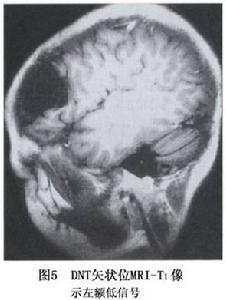

DNT少見,自Daumas-Duport首批報導39例以來,以後均只有零星個例報導腫瘤多見於兒童,但也有青年患者,男女性無明顯差異。DNT好發於幕上,62%~78%位於顳葉,其餘幾乎均位於額葉。有人報導DNT占20歲以下組神經上皮性腫瘤的1.2%全年齡組的0.63%

胚胎髮育不良性神經上皮腫瘤病程長,常在幼年或年輕時發病,主要表現為複雜性的局灶性癲癇發作。癲癇常為頑固性而不易控制。腦電圖常有病灶部位的癲癇波存在。因本病生長緩慢,局部顱骨可受壓變薄。

對於胚胎髮育不良性神經上皮腫瘤手術切除來消滅致病灶是有效方法,手術目的是切除病灶控制癲癇發作可作病灶全切除,或是對發育不良的皮質及部分病灶切除,一般術後癲癇能完全消失,不需術後放療或化療,

胚胎髮育不良性神經上皮腫瘤預後好,很少復發,不影響病人生存。